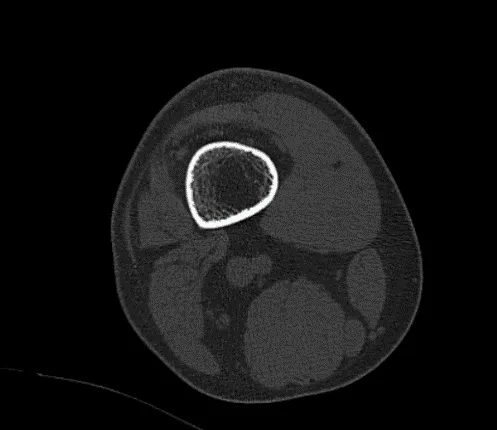

The patient was seen for post op follow up checkup and he still has pain. He got a CT scan done of his knee. It showed status post comminuted fracture of ACL footprint and postsurgical reimplantation of PCL attached to the largest fracture fragment. No evidence for bony union is evident.

No interval change is seen in the position of the large and small fragments. There is a thickened appearance of the ACL outlined. No interval changes in the appearance of tiny fracture fragments peripheral to medial condyle, peripheral to lateral tibial plateau and slight residual osteochondral irregularity of peripheral posterior lateral plateau.

CT-Right Knee Non-contrast